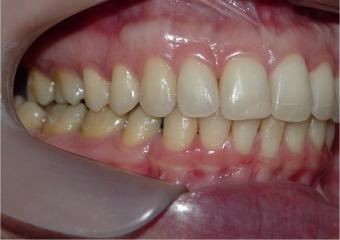

Perfil inicial